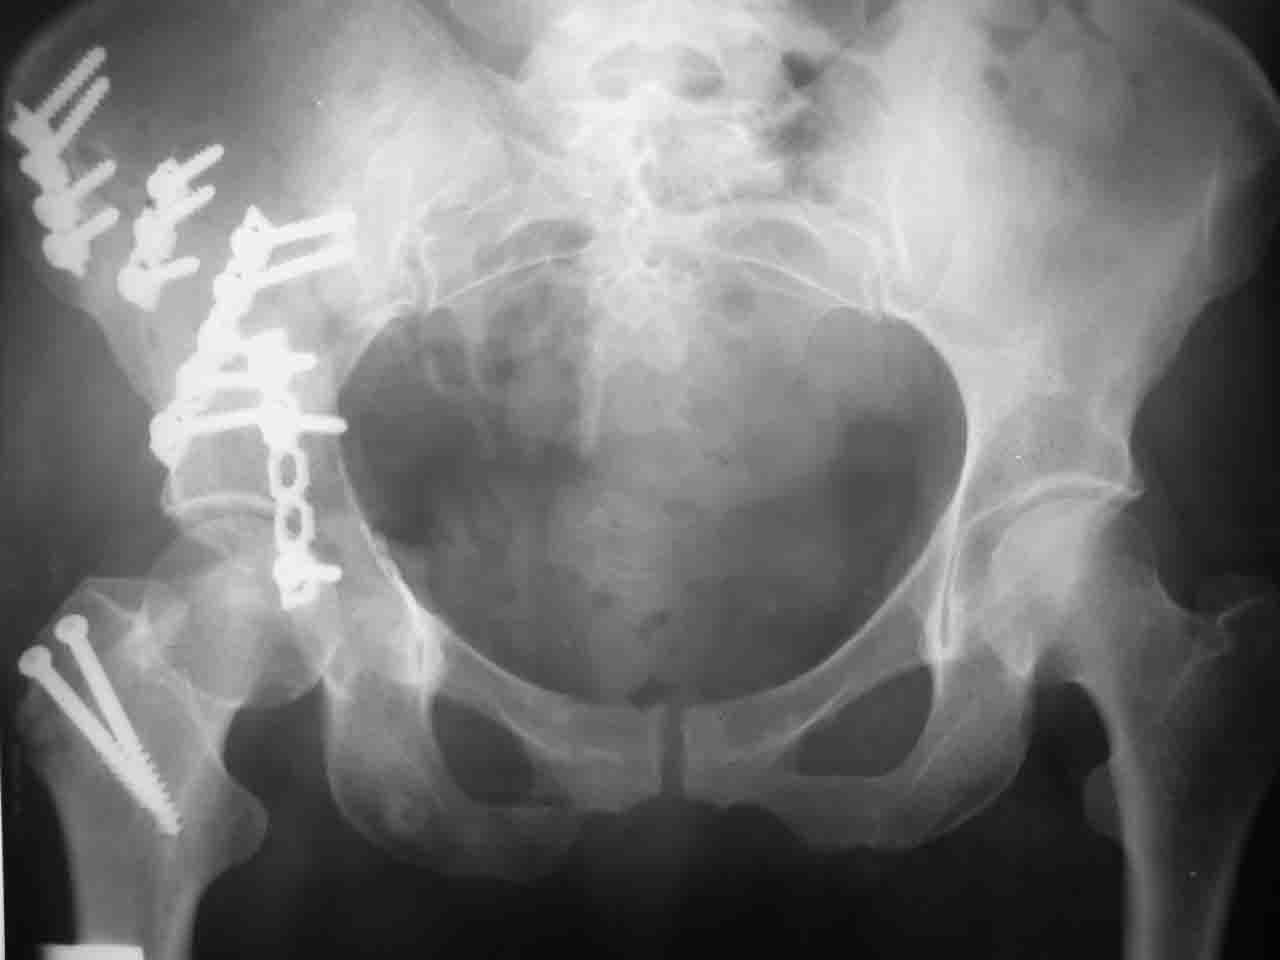

Вопрос доступа к вертлужной впадине при остеосинтезе задача не простая. Конечно, у Летурнеля и Тайла всё давно описано, нам остается только брать на вооружение. Но сами понимаете, что не бывает двух одинаковых ситуаций, поэтому в каждом случае вопрос решается сугубо индивидуально. Наша главная цель - восстановить анатомию с нанесением минимальной дополнительной травмы тазобедреннному суставу, думаю с этим никто не поспорит. Расширенный илиофеморальный доступ уж слишком травматичен (как сказал один коллега "таз лежит отдельно, больной отдельно").Стоит ли делать из пациента анатомический препарат для того чтобы легче ориентироваться. Да и нужно ли собирать всю "мозаику"? Мы применяли при таких операциях своеобразную операционную хитрость - сначала устраняли грубое смещение крыла под гребнем с фиксацией так называемой "плавающей" пластиной (временно фиксированной на двух винтах)- доступ или продлевали боковой, или делали небольшой дополнительный разрез над гребнем. Это позволяло устранить грубое смещение и захождение отломков тела повздошной кости, что значительно облегчало репозицию и остеосинтез впадины над сводом. Основное внимание конечно же уделяли нагружаемому задне-верхнему отделу. Сообщите ваш адрес, пришлю схемы и рентгенограммы.